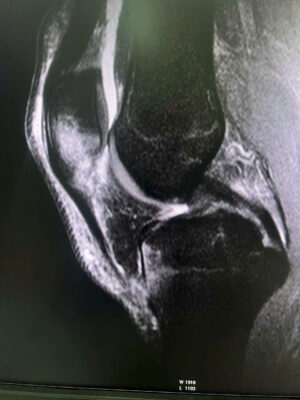

1. MỞ ĐẦU 📚Tổn thương phối hợp giữa dị vật nội khớp háng và mạc giữ bánh chè – đùi trong (Medial Patellofemoral Ligament – MPFL) là tình huống hiếm gặp trong chấn thương chỉnh hình. 👉Các biểu hiện lâm sàng thường không đặc hiệu, dễ bị che lấp bởi triệu chứng đau đa vùng sau chấn thương, dẫn đến nguy cơ bỏ sót tổn thương nội khớp nếu không được đánh giá hình ảnh đầy đủ. 💥Việc phối hợp giữa khám lâm sàng tỉ mỉ và chẩn đoán hình ảnh chuyên sâu (CT, MRI) đóng vai trò quyết định trong việc phát hiện sớm, định hướng điều trị và tiên lượng phục hồi chức năng vận động cho người bệnh. 2. CA LÂM SÀNG 📚 Bệnh nhân nam, sau chấn thương biểu hiện đau vùng háng và gối phải, hạn chế vận động chi dưới cùng bên, đã khám ở BV tuyến trước không xác định được tổn thương. Đêm ngày 03/10, chuyển đến Bệnh viện Quân y 17, qua khám lâm sàng ghi nhận đau sâu vùng háng, đau mặt trong gối khi vận động gấp duỗi, khi sờ ấn, không có biến dạng. 📚Hình ảnh CT scan khớp háng phát hiện một dị vật nhỏ nằm trong ổ khớp háng phải, nghi là mảnh xương vỡ gây kẹt khớp sau chấn thương. MRI khớp gối phải cho thấy tổn thương mạc giữ bánh chè – đùi trong (MPFL) tại chỗ bám vào xương bánh chè, kèm tràn dịch khớp nhẹ. 👉 Nhờ phối hợp chặt chẽ giữa bác sĩ lâm sàng và bác sĩ chẩn đoán hình ảnh, tổn thương phối hợp hiếm gặp này được xác định chính xác, giúp tránh bỏ sót dị vật nội khớp và mô mềm quanh gối khó phát hiện nếu chỉ dựa vào thăm khám. 👉Bệnh nhân được dự kiến lấy dị vật nội khớp háng bằng kỹ thuật ít xâm lấn, nội soi kết hợp màn hình tăng sáng hỗ trợ, bảo tồn mạc giữ khớp bánh chè – đùi trong do không gây di lệch xương bánh chè. 3. BÀN LUẬN 👉 Dị vật nội khớp háng là tổn thương ít gặp, thường thứ phát sau chấn thương gãy xương vùng chậu – ổ cối. Trong khi đó, rách MPFL là tổn thương hay gặp nhất trong trật khớp, gãy xương bánh chè cấp, nhưng hiếm khi xuất hiện đồng thời với dị vật nội khớp háng. Khi hai tổn thương này cùng tồn tại, triệu chứng thường chồng lấp, dễ dẫn đến chẩn đoán không đầy đủ hoặc điều trị chưa triệt để.

✓ Theo Guerrero và cộng sự, MRI là phương tiện hiệu quả nhất để nhận diện tổn thương MPFL và phân loại mức độ rách (tại điểm bám vào bánh chè, tại xương đùi hoặc rách đoạn giữa), trong khi CT giúp phát hiện chính xác các mảnh xương tự do hoặc dị vật trong khớp [3]. ✓ Các tác giả Selmene MA (2022) và Davis ES (2019) cũng khẳng định rằng kỹ thuật lấy dị vật nội khớp háng ít xâm lấn hoặc có hỗ trợ C-arm giúp giảm sang chấn mô mềm và rút ngắn thời gian hồi phục [1],[2]. ✓ Trong báo cáo này, việc phối hợp CT – MRI đã cho phép phát hiện đầy đủ cả hai tổn thương, đồng thời định hướng phẫu thuật hợp lý: lấy dị vật nội khớp nội soi, đồng thời khâu phục hồi cấu trúc mạc giữ khớp bánh chè – đùi trong nếu cần thiết. ✓ Cách tiếp cận này giúp hạn chế nguy cơ bỏ sót tổn thương nhỏ, bảo tồn cấu trúc khớp và phục hồi sớm chức năng vận động. 4. KẾT LUẬN ✓Tổn thương phối hợp giữa dị vật nội khớp háng và rách mạc giữ bánh chè – đùi trong là hiếm gặp và có thể bị bỏ sót nếu không được đánh giá toàn diện. ✓Sự phối hợp chặt chẽ giữa bác sĩ lâm sàng và chẩn đoán hình ảnh là yếu tố then chốt giúp chẩn đoán chính xác, lựa chọn chiến lược điều trị hợp lý, mang lại kết quả phục hồi tối ưu cho người bệnh. 📚Trường hợp tại Bệnh viện Quân y 17 là minh chứng cho năng lực chuyên sâu của đơn vị trong chẩn đoán và xử trí các tổn thương chấn thương chỉnh hình phức tạp, góp phần nâng cao chất lượng điều trị và an toàn người bệnh. 5. TÀI LIỆU THAM KHẢO [1]. Selmene MA, et al. Minimally invasive removal of intra-articular hip fragments. [Journal of Orthopaedic Case Reports]. 2022. [2]. Davis ES, et al. A novel technique to remove posterior intra-articular hip foreign bodies via anterior approach. Tech Orthop. 2019;34(4):302-306. [3]. Guerrero P, Li X, Patel K, Brown M, Busconi BD. Medial patellofemoral ligament injury patterns and associated pathology in lateral patella dislocation: an MRI study. Sports Med Arthrosc Rehabil Ther Technol. 2009;1:17. [4]. Conlan T, Garth WP Jr, Lemons JE. Evaluation of the medial soft tissue restraints of the extensor mechanism of the knee. J Bone Joint Surg Am. 1993;75:682-693. [5]. Nomura E, Inoue M, Osada N. Anatomical analysis of the medial patellofemoral ligament of the knee, especially the femoral attachment. Knee Surg Sports Traumatol Arthrosc. 2005;13:510-515. [6]. Smith A, et al. Medial patellofemoral ligament reconstruction: a systematic review. Orthop J Sports Med. 2024;12(1):1-10.